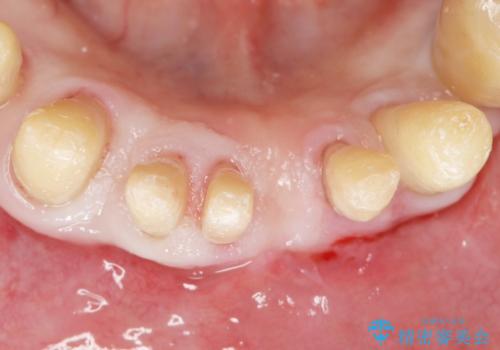

精査したところ、全顎的な重度の歯周病により下顎前歯に激しい動揺を認めました。

骨吸収と動揺が著しい前歯1本(左下1)のみ抜歯しております。

歯も神経も残したいという患者様のご希望により、補綴前に部分矯正を行っております。